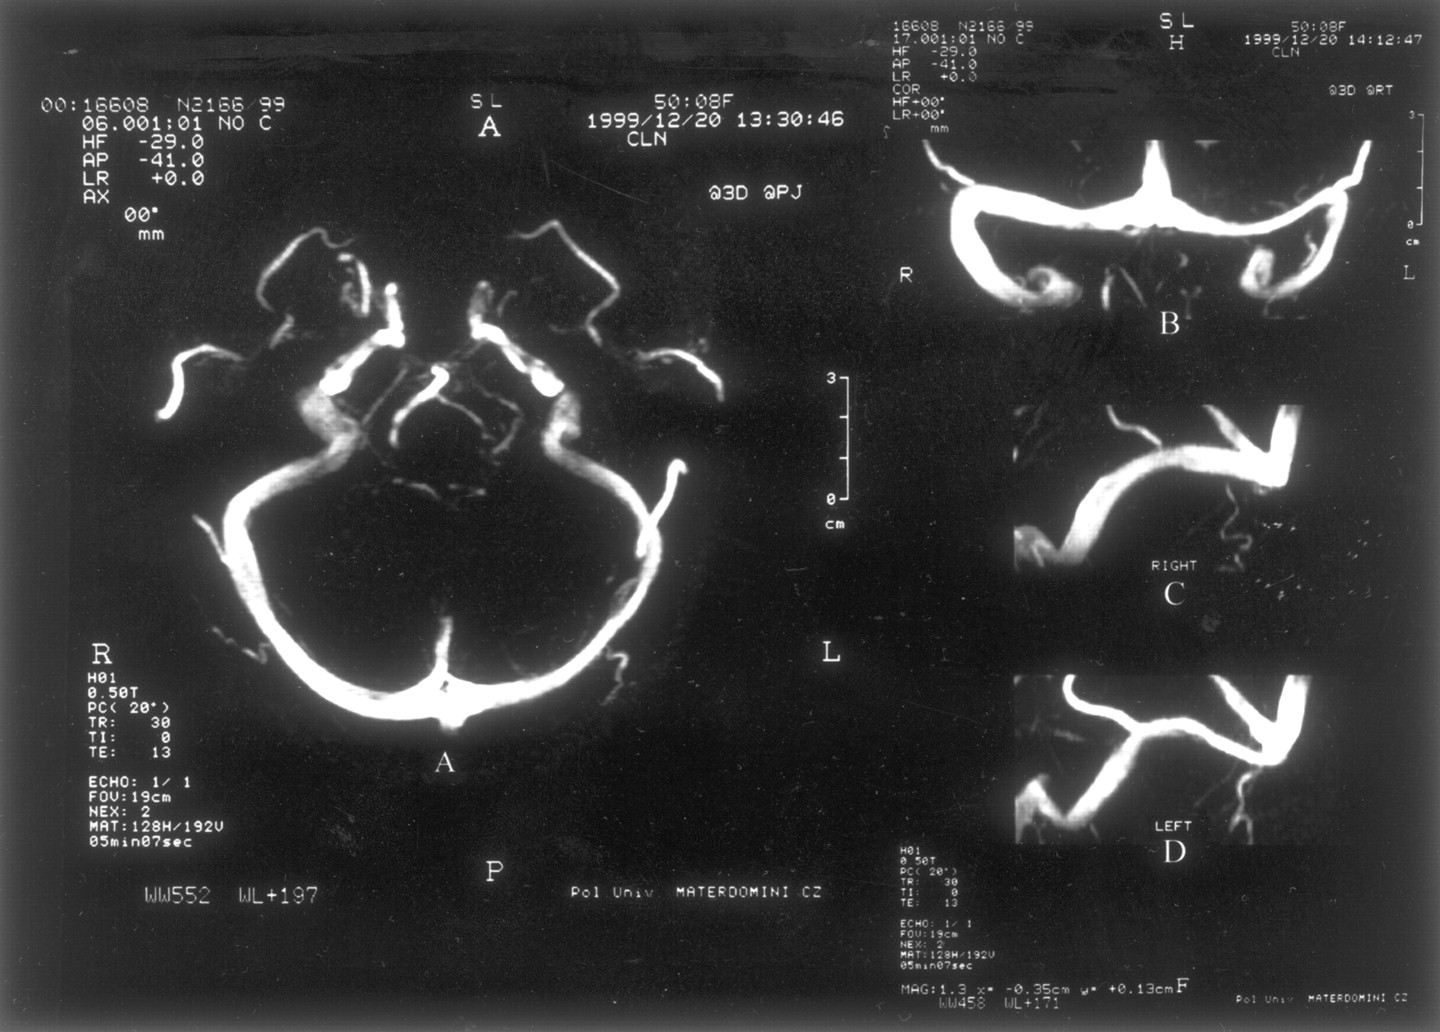

我们调查了111例正常脑脊液压力188金宝慱官网下载(60 - 192毫米范围H2O;意思是135;SD 33)。所有受试者正常的大脑直接上级矢状先生和鼻窦,盖伦的静脉,和内部脑静脉被认为在所有情况下,而枕窦是只有5%的病人。MRV显示正确,左,或共显性的TS在51%,18%,31%的病例。六十六例正常MRV (图1)而45主题显示干扰的一个或两个TS流。流的扰动分类为流动间隙如果缺乏信号流的长度小于或等于三分之一窦。在一个TS流差距观察静脉造影照片先生在29.7% (33/111);188金宝慱官网下载其中,36.4%(12/33)发生在占主导地位的TS。剩下的21例焦流缺口被认为在非惯用(42.4%,14/33)TS的窦或被认为是共显性的(21.2%,7/33)。流缺口位于近端部分TS在15%(5/33)的被试(图2),而流量差距mid-lateral部分TS中85%(28/33)的人(图3)。关于后个人,其中75%(21/28)有焦空白暗示蛛网膜颗粒的流动。缺乏信号流在一个整个TS在9%(10/111)的病例。188金宝慱官网下载值得注意的是,只有2个人(1.8%)焦TS流缺口。

目前的研究表明,在一个TS流差距MRV是一种常见的发现在主题与正常脑脊液压力。的确,在我们的系列在一个TS流差距发生在29.7%的受试者,表明在一个TS流缺口出现在MRV可能往往缺乏病理意义。我们的研究结果还表明,在21个33个科目(63.6%)的流量差距的非惯用或共显性的TS,而在12的33(36.4%)例发生在占主导地位的TS流差距。在方差与我们的研究结果,一些作者3发现流差距在MRV从未见过在健康受试者的占主导地位的TS。我们的数据和上述研究之间的差异可能是由于不同的技术。我们使用一个三维相位对比MRV而其他作者3使用一个二维TOF MRV,可能低估了流的干扰技术在脑静脉窦。6有趣的是,在当前的研究中只有2 111例(1.8%)显示在TS流差距,表明两国流扰动的TS很188金宝慱官网下载少发生在个体与正常脑脊液压力。同意这个结果,我们先前表明,大多数科目与慢性每日头痛两TS流有差距的三维相位对比MRV也孤立颅内高血压有或没有视神经乳头水肿。5、7⇓这一发现也证实了最近的一项研究8特发性颅内高血压患者中显示,三维相位对比MRV, TS流差距。在这个病人,静脉造影术和测压法显示障碍物的远端部分TS的近端阻塞,提高压力和膨胀的TS支架减少压力梯度和脑脊液压力。最近的一项研究中,使用auto-triggered elliptic-centric-ordered三维gadolinium-enhanced先生造影术(ATECO MRV),表明两国sinovenous狭窄发生在特发性颅内高血压患者的93%。9虽然ATECO MRV可以提供相当大的好处/飞行时间技术先生,ATECO MRV方法的一个缺点是,它依赖于丸造影剂管理,使过程更加复杂。总的来说,这些发现表明,TS的双边障碍,通过改变大脑静脉引流,可导致静脉高血压,轮流增加脑脊液压力。

值得注意的是流差距主要被发现在TS的mid-lateral部分85%的个体,而只有15%的情况下显示的近端部分TS流差距。因为蛛网膜颗粒通常发生在TS的mid-lateral部分,可以假设在某些个人突出蛛网膜颗粒(或血栓形成在这些解剖结构)可能产生相对腔妥协从而导致压力梯度或扰流。同意这个结果,一些作者10显示硬脑膜的鼻窦的小型或大型蛛网膜颗粒19 29尸体标本;这些发现的绝大多数在TS左侧优势和优惠的本地化mid-lateral窦的一部分。同意这个结果,增强对比度MRV或对比增强CT脑鼻窦的研究显示蛛网膜颗粒的发生在13%和24%的主题。10不同于差距发生在mid-lateral部分TS流,流缺口位于鼻窦的近端部分可能是由于近端发育不全的TS。最后,10 111例(9%)受试者缺乏流信号在整个TS。整个TS的发育不全可能解释这一发现。188金宝慱官网下载